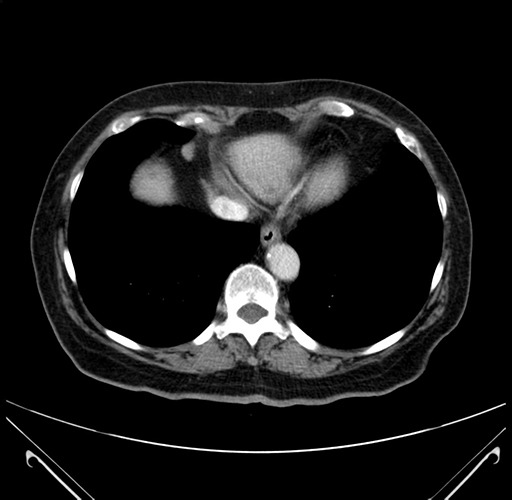

Pre-Chemo: Axial Venous

Axial Venous